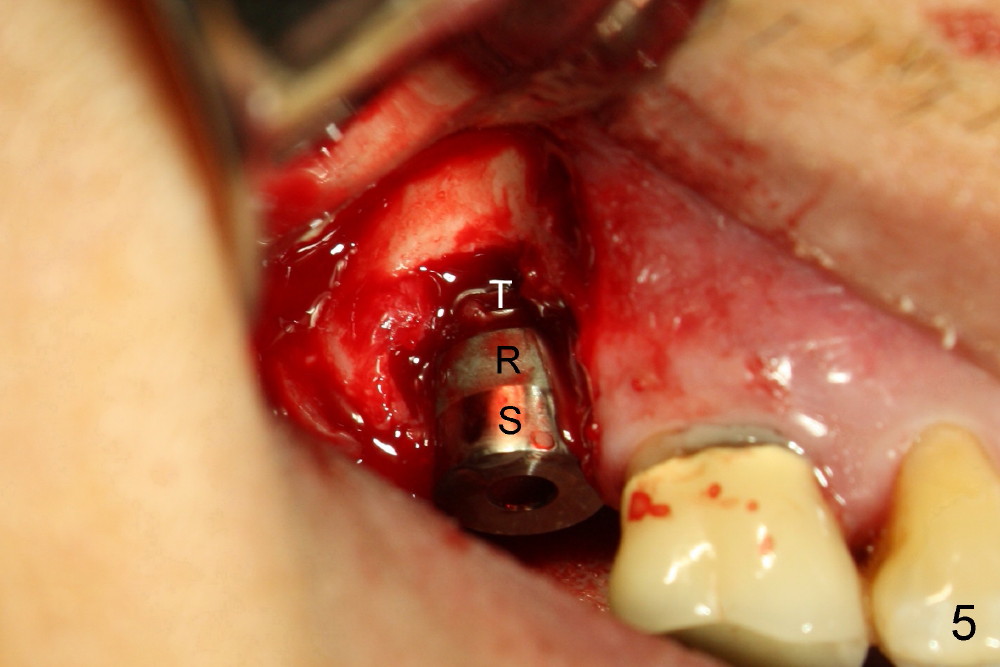

Periimplantitis develops with bone loss 4 years 5 months post cementation (Fig.15). It appears that the implant should be removed (Fig.16, unipost cemented with Ketac, prepare special screw driver after handpiece making a slot), followed by bone graft (Fig.17 red circles), particularly mesial to #1 implant and PRF. Prepare Titanium brush to clean the exposed implant threads of #1 implant. When the defect heals (with increased bone height, Fig.18 greyish area), place a smaller implant (green) with guide.